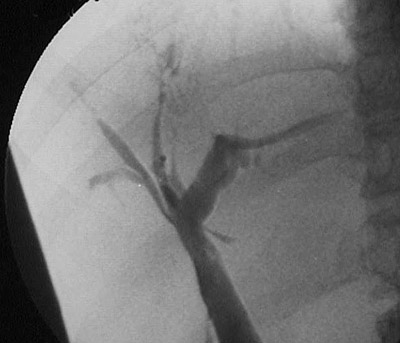

| Here is another view from a cholangiogram to demonstrate a beaded pattern and ductular narrowing and pruning from irregular segmental strictures with fibrosis of bile ducts in a case of sclerosing cholangitis. Patients with inflammatory bowel disease, and ulcerative colitis in particular, can develops sclerosing cholangitis. |